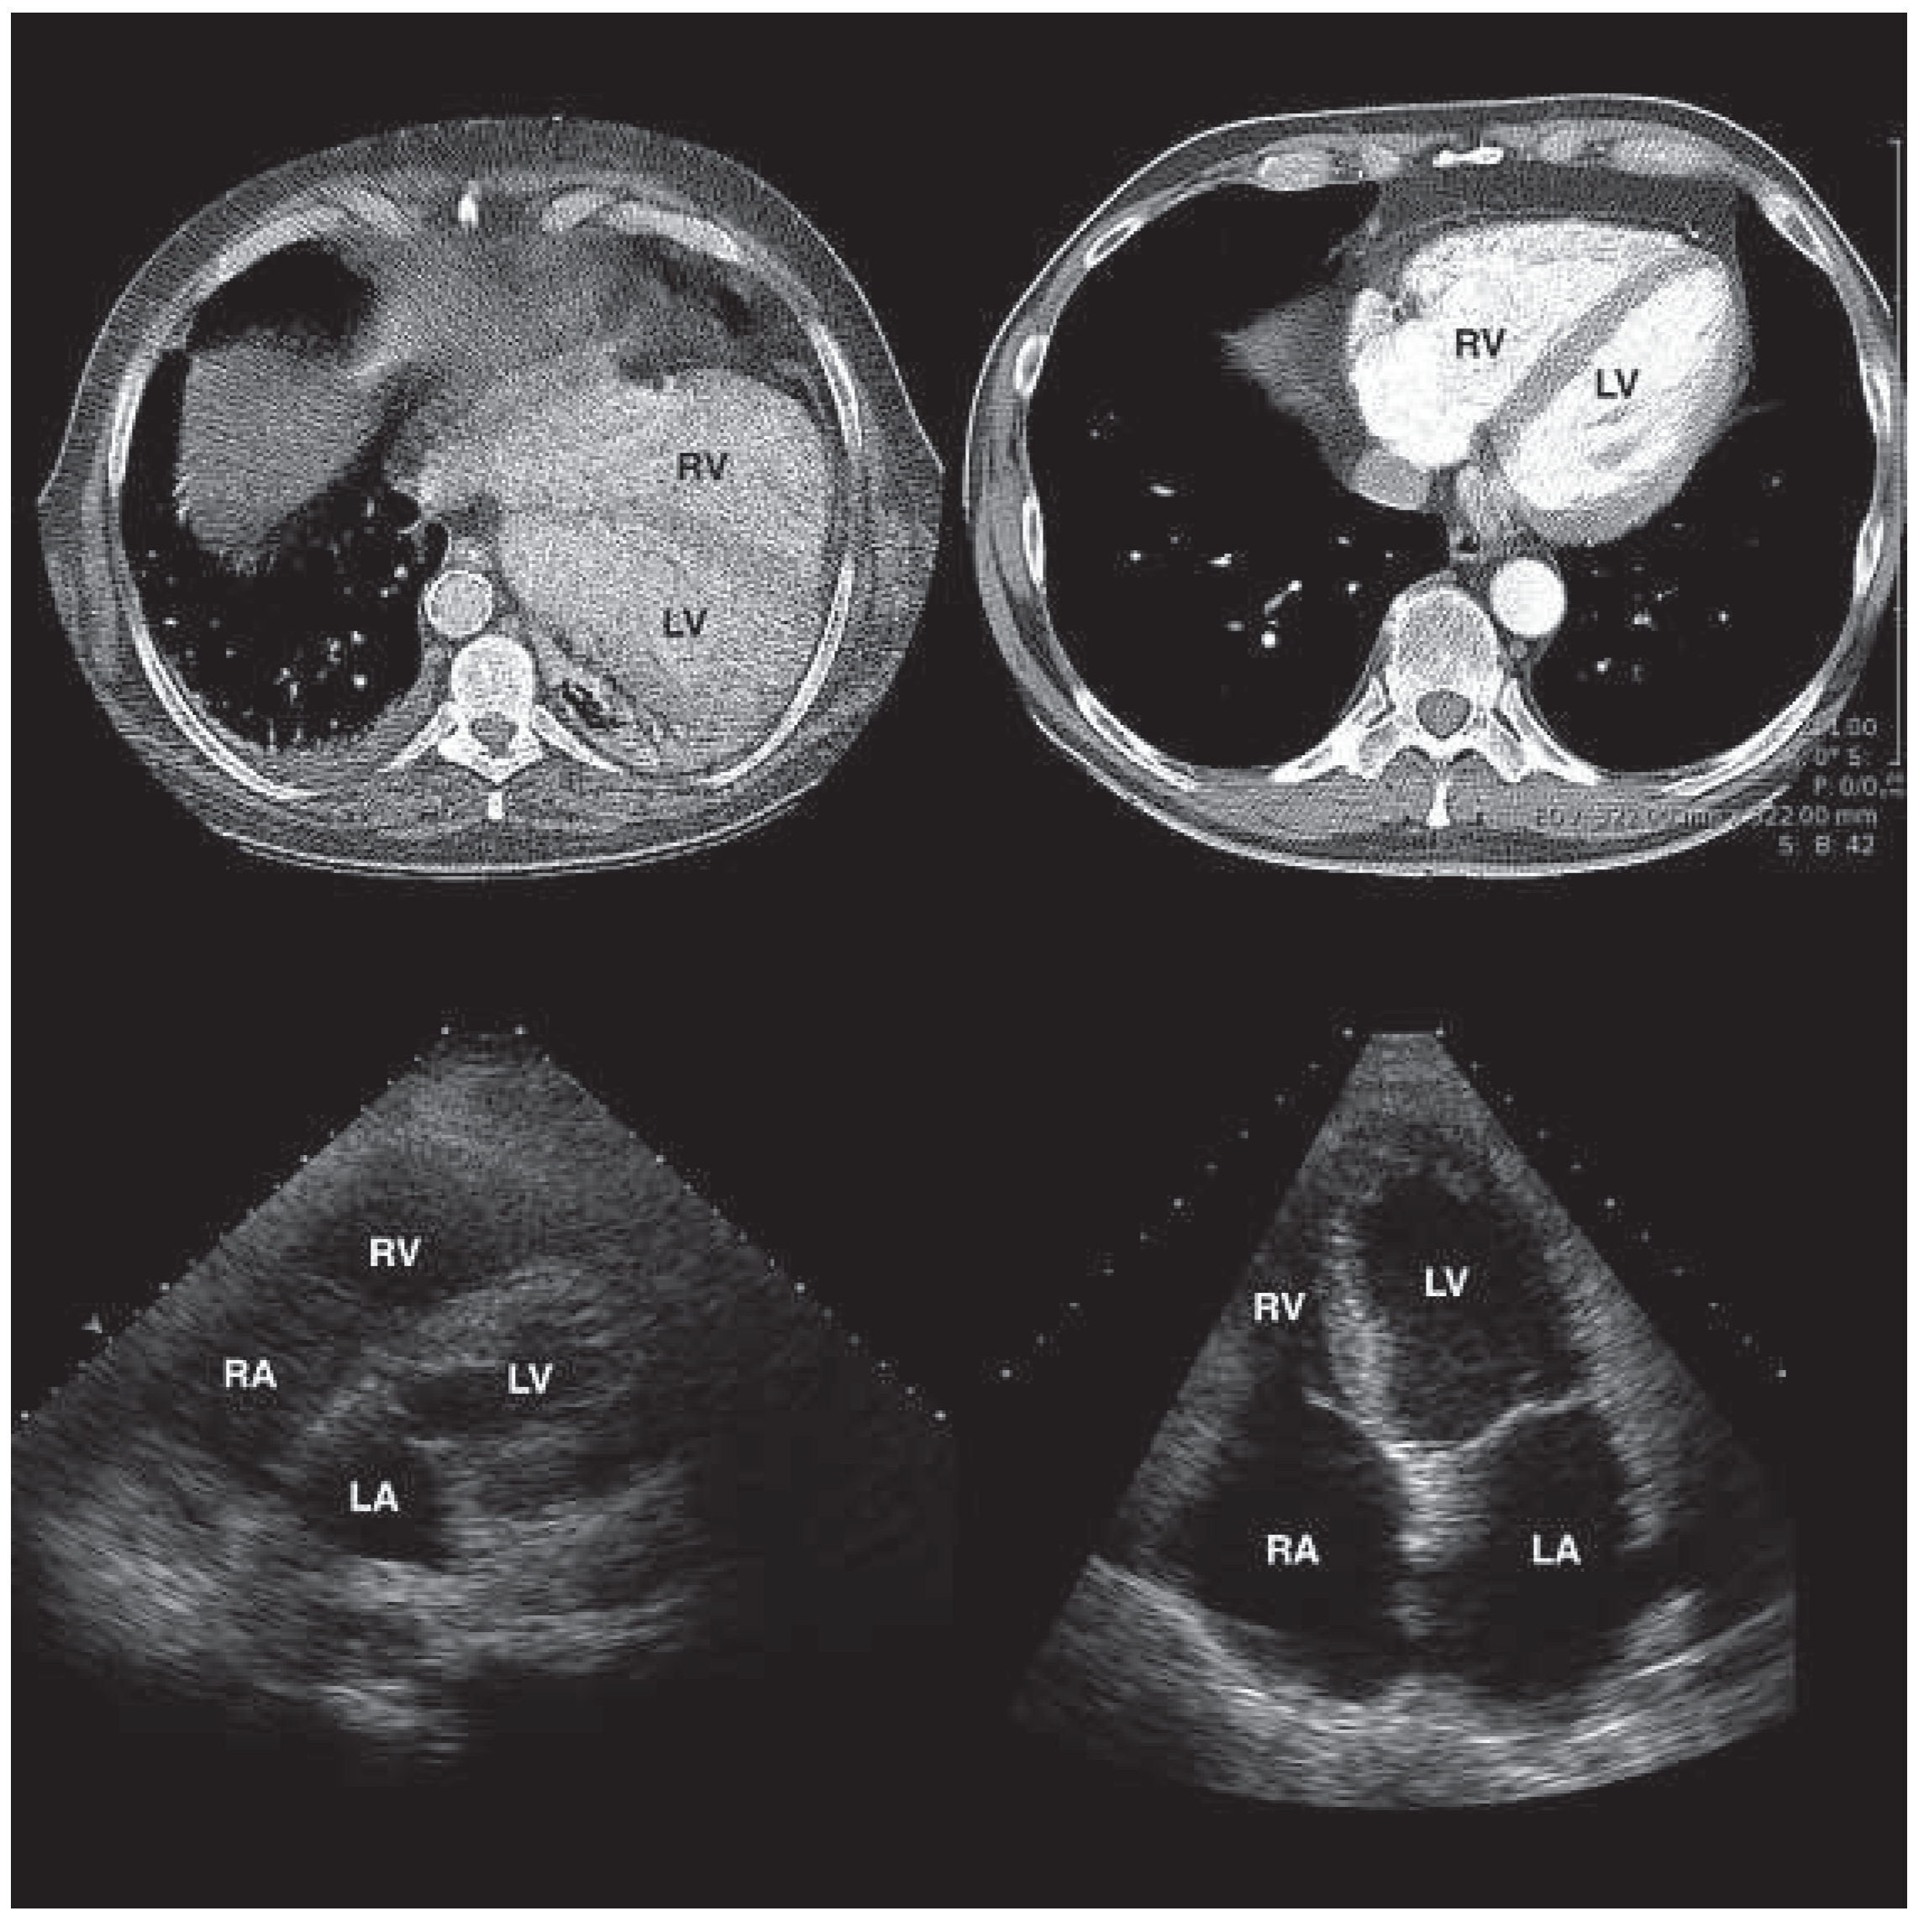

Lost in Space - Left Lateral Cardiac Displacement Due to an Unusual Cause